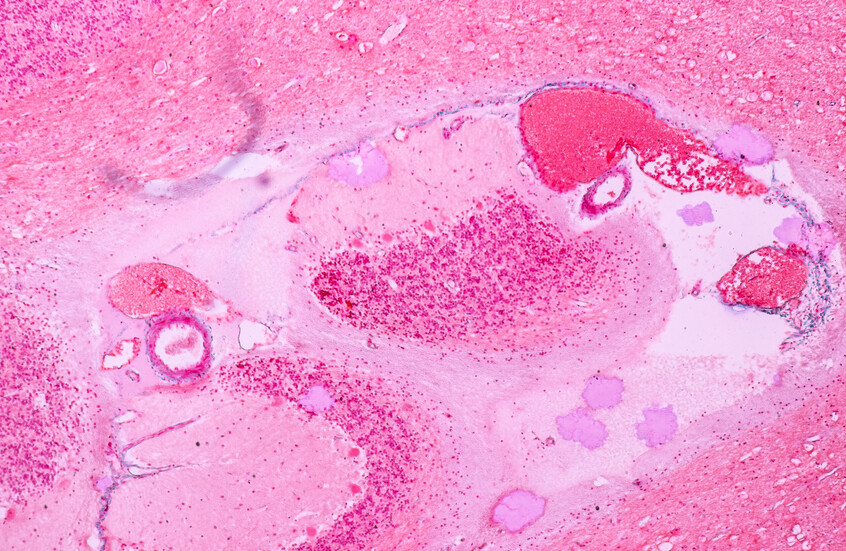

باحثون: خضار ترتبط "بارتفاع" خطر الإصابة بسرطان المعدة!

يصعب علاج السرطان بمجرد انتشاره، لذا فإن الاكتشاف المبكر هو المفتاح. والأفضل من ذلك، يمكنك تعديل خطر الإصابة بالمرض المميت في المقام الأول.

وتنمو الخلايا السرطانية وتتكاثر بسرعة في الجسم، مما يجعل الجهود المبذولة لمنعها غير مجدية. وبطبيعة الحال، الوقاية خير من العلاج. وعلى الرغم من عدم وجود طريقة للوقاية من السرطان أو علاجه، إلا أنه يمكنك تعديل مخاطر إصابتك.

ويوجه الباحثون انتباههم بشكل متزايد إلى الدور الذي تلعبه مكونات غذائية معينة في التأثير على مخاطر الإصابة بالسرطان. وواحدة من أكثر الارتباطات إثارة للدهشة تم رسمها بين تناول الخضروات المخللة وخطر الإصابة بسرطان المعدة. والخضار المخللة هي تلك المنتجات التي يتم تحضيرها بواسطة حمض صالح للأكل (يضاف أو يتشكل عن طريق التخمير) ويرجع الحفظ، جزئيا على الأقل، إلى وجود هذا الحمض.

وكتب باحثون في مجلة Cancers التي راجعها الزملاء: "اقترحت زيادة خطر الإصابة بسرطان المعدة بسبب تناول الخضروات المخللة والأسماك المملحة، ومع ذلك فإن عدم وجود ارتباط بين الجرعة والاستجابة يستدعي إجراء تحليل كمي".

كما أن العلاقة بين الجرعة والاستجابة هي علاقة ترتبط فيها مستويات التعرض المتزايدة إما بزيادة أو انخفاض مخاطر النتيجة. وفي هذه الحالة، تكون النتيجة زيادة خطر الإصابة بالسرطان.

وحقق الباحثون في ارتباط تناول الخضار المخلل والأسماك المملحة بسرطان المعدة في دراسة الوبائيات الجينوم الكوري ودراسة السرطان متعددة المراكز الكورية.

وكتبوا: "في هذا التحليل التلوي المنهجي للدراسات المستقبلية، وجدنا ارتباطا مهما بين زيادة مخاطر الإصابة بسرطان المعدة وزيادة تناول الخضروات المخللة".

ولاحظ الباحثون أن معدل الإصابة بسرطان المعدة كان أعلى بمقدار 1.15 مرة مقابل زيادة قدرها 40 غم/يوم في تناول الخضروات المخللة وأعلى بمقدار 1.24 مرة، مقارنة بأعلى معدل مع أقل تناول.

وخلص الباحثون إلى أن "نتيجة التحليل التلوي للجرعة والاستجابة التي أجريناها تعزز التحليلات التلوية السابقة، والتي أظهرت زيادة خطر الإصابة بسرطان المعدة ، مقارنة بين أعلى وأقل تناول للخضروات المخللة والأسماك المملحة. والنتائج التي توصلنا إليها تدعم الدليل على أن تناول كميات كبيرة من الخضار المخلل والأسماك المملحة يرتبط بارتفاع مخاطر الإصابة بسرطان المعدة".

المصدر: إكسبريس